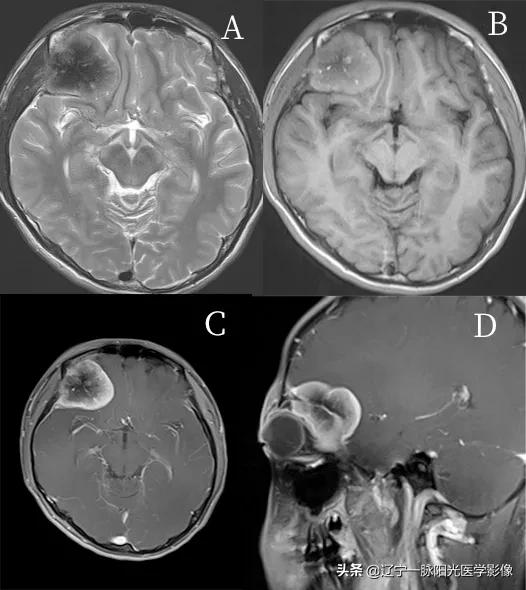

影像所见:

右眼肌椎外上方见团块状异常信号影,边界尚清,范围约 5.0 cm×3.8 cm×3.2 cm,内部信号欠均匀

图 B 轴位 T1WI 信号介于脑白质与脑灰质,内可见斑点状高信号,图 A 轴位 T2WI 等低信号,内部低信号,水抑制低信号

图 C、D 增强后病灶明显强化,不均匀,邻近脑膜可见强化;右侧上斜肌及外直肌增粗,并受压移位,右眼球受压突出眼眶,右额叶呈弧形推压,边界清楚

最终病理诊断:骨母细胞瘤样骨肉瘤